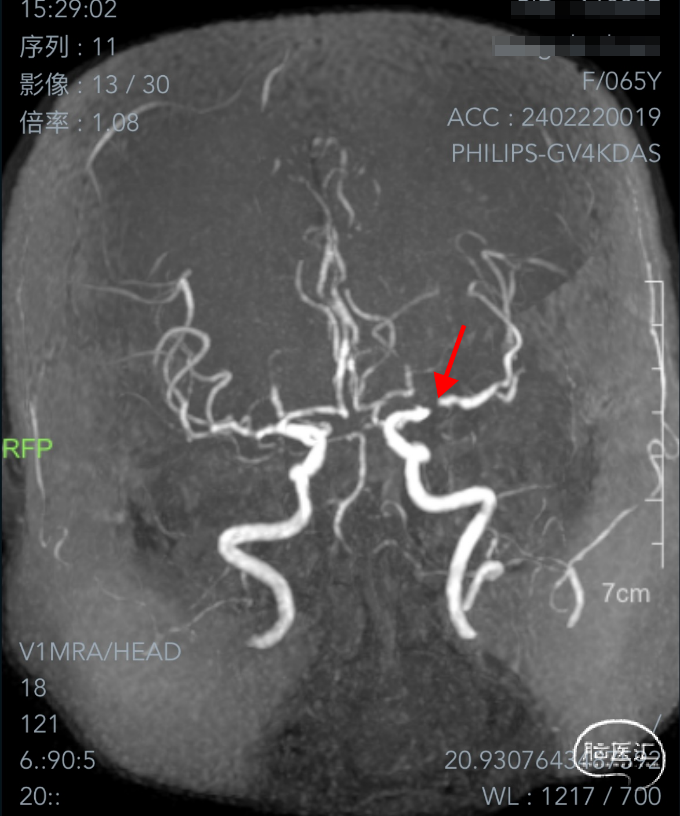

➤2024.3.2 DSA

左侧大脑中动脉M1段重度狭窄。

II型弓,左侧大脑中动脉M1段重度狭窄(几近闭塞)。